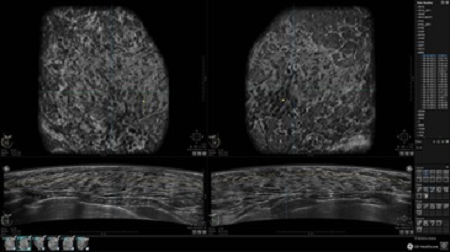

GE INVENIA ABUS – это современный УЗИ аппарат, который создан для точной и эффективной диагностики сканирования с высокой плотностью молочных желез. Выявляемость патологий раковых и предраковых стадий заболевания составляет 55%, что в конечном счете позволяет ставить врачу точные и своевременные диагнозы. Традиционные методы использования маммографии не показывают такой выявляемости, ограничиваясь лишь 3-38%.

УЗИ-аппарат GE INVENIA ABUS позволяет проводить максимально операторонезависимые процедуры, что значительно снижает риск неправильной постановки диагноза и сопутствующие издержки на обработку информации. Система готовит отчет в течение 3-х минут после сканирования, это безусловное преимущество по сравнению с обычным УЗИ сканером.

• Получение объемных 3D изображений с возможностью покадрового просмотра

• Отображение объемных 3D ультразвуковых изображений, которые состоят из традиционных поперечных и воссозданных коронарных и сагиттальных проекций

• Многооконный просмотр: 4 - 12 изображений

• Стандартизованная ориентация изображения: «толстый срез» в коронарной плоскости; поперечная; сагиттальная плоскость; радиальный и антирадиальный поворот изображения; просмотр исключительно области интереса